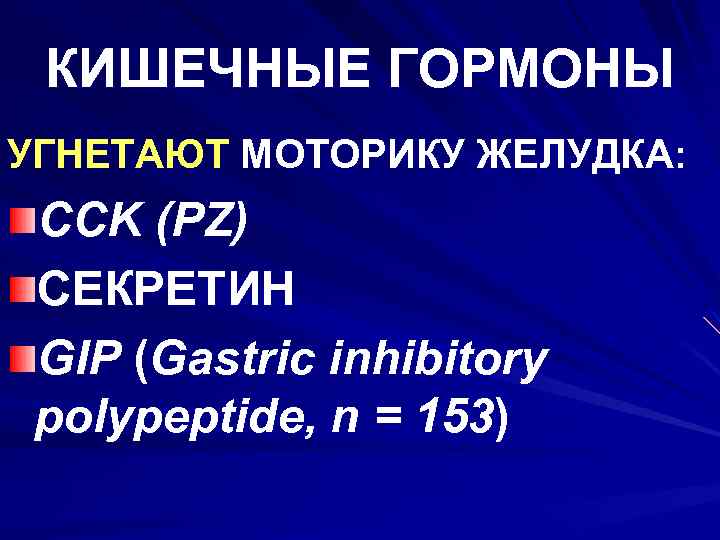

КИШЕЧНЫЕ ГОРМОНЫ УГНЕТАЮТ МОТОРИКУ ЖЕЛУДКА: CCK (PZ) СЕКРЕТИН GIP (Gastric inhibitory polypeptide, n = 153)

КИШЕЧНЫЕ ГОРМОНЫ УГНЕТАЮТ МОТОРИКУ ЖЕЛУДКА: CCK (PZ) СЕКРЕТИН GIP (Gastric inhibitory polypeptide, n = 153)